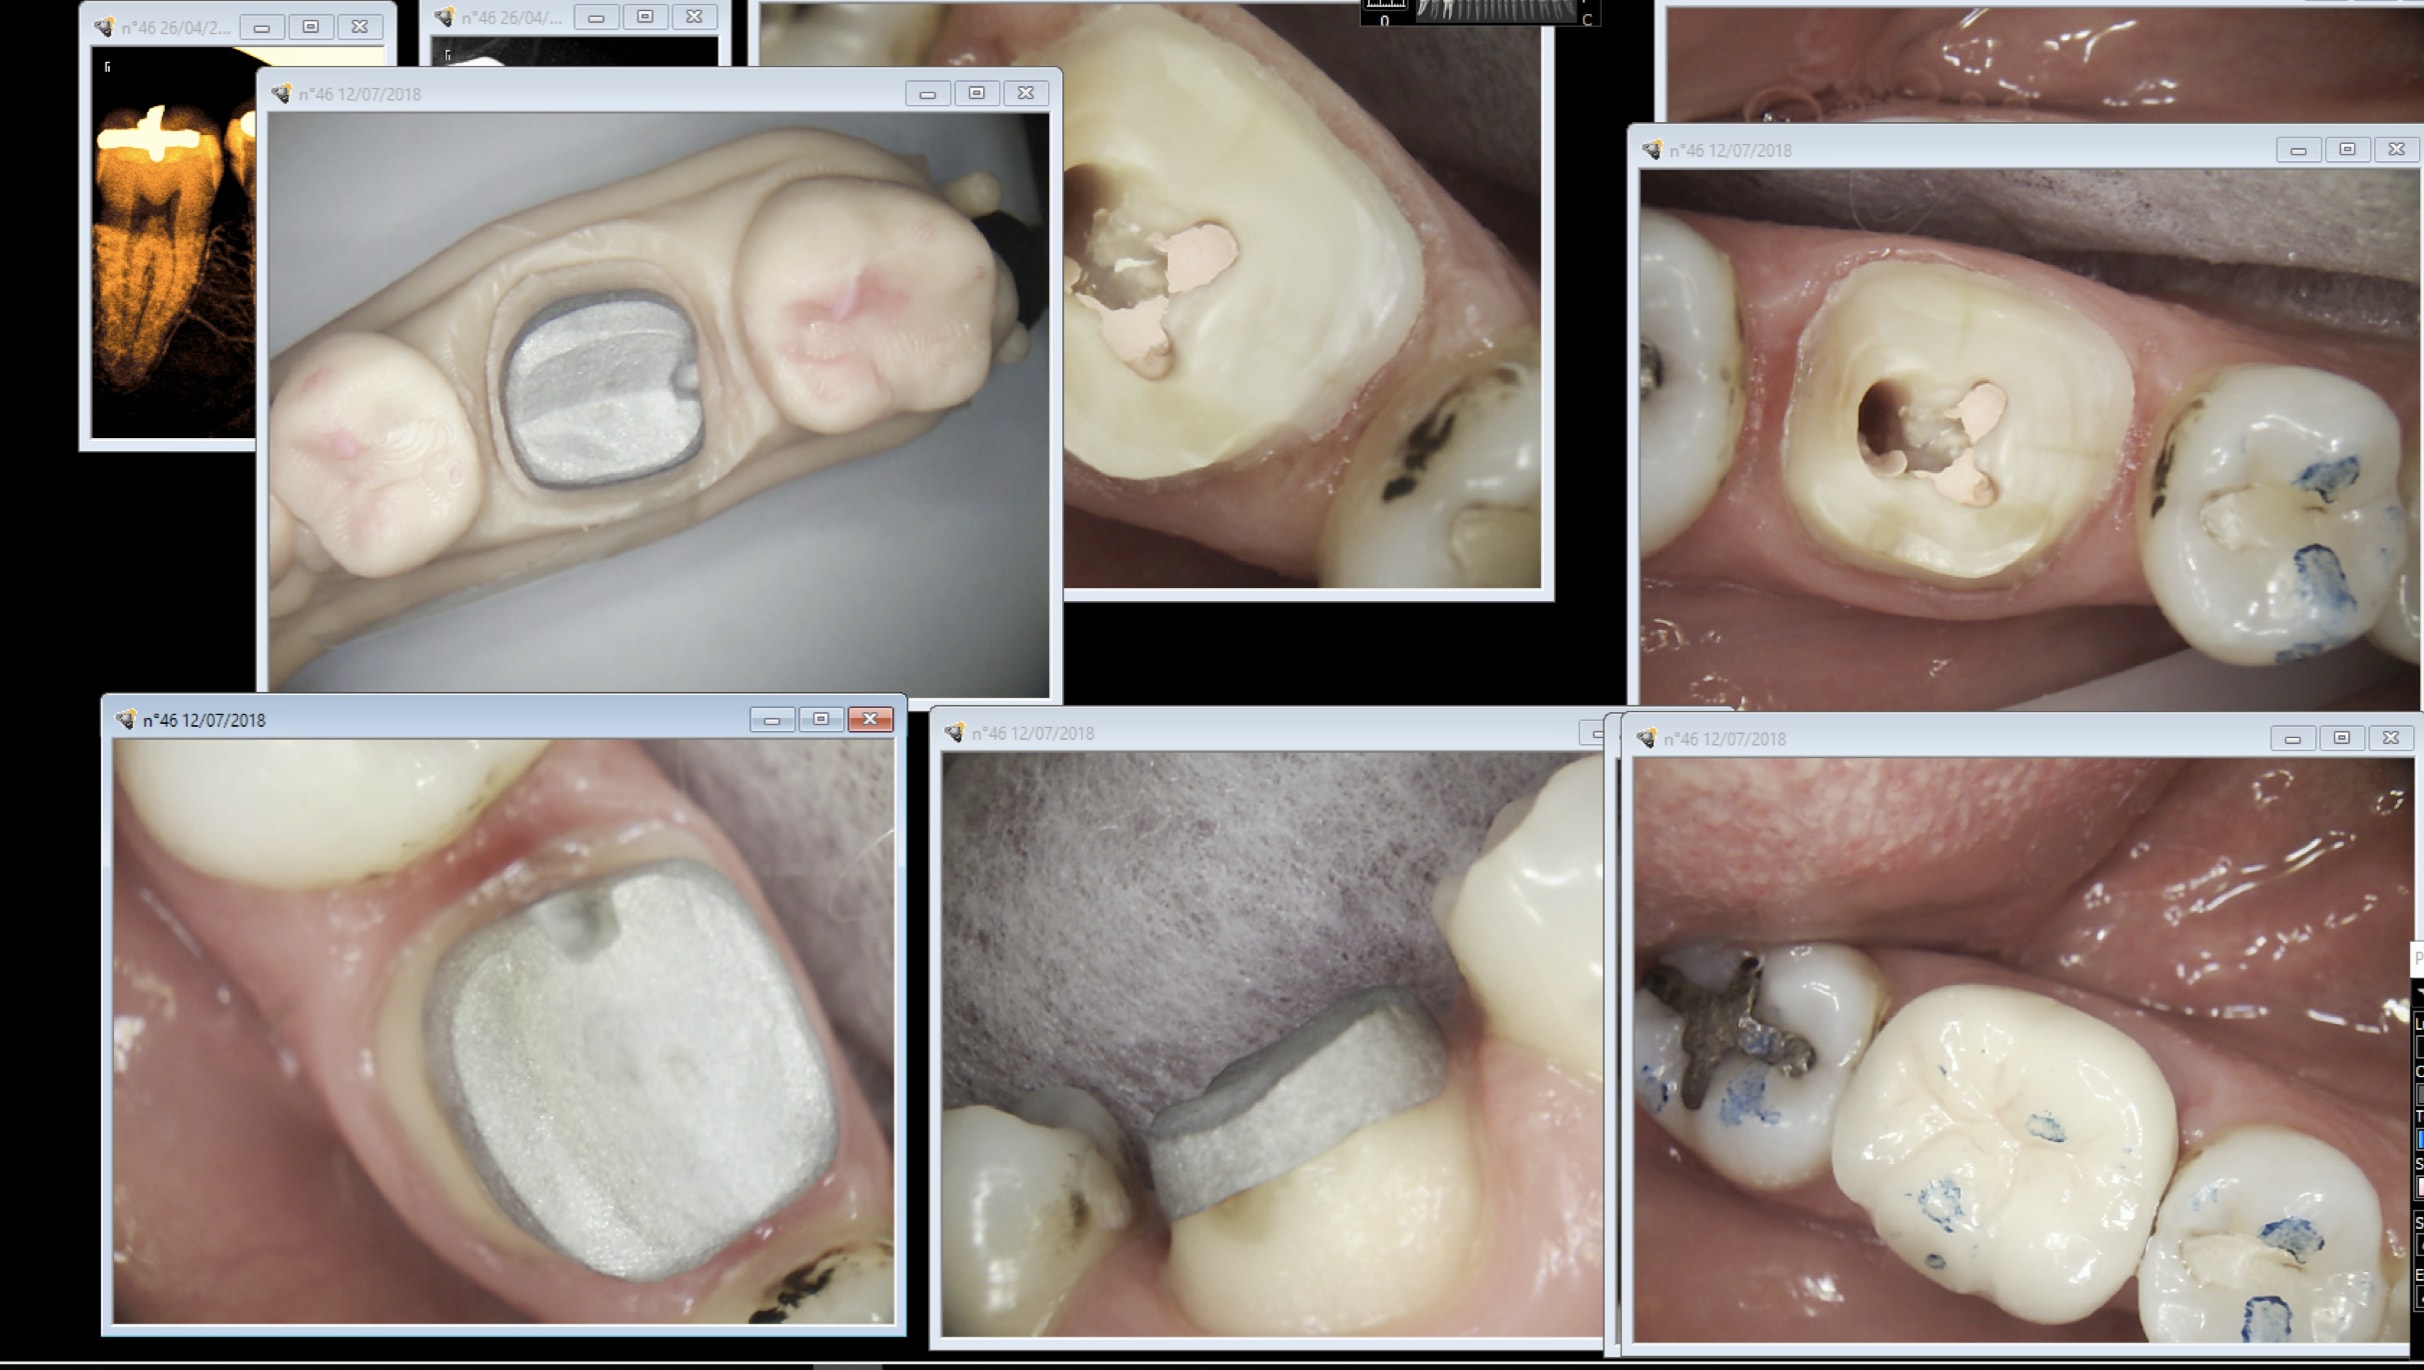

Capture d écran 2018 07 14 11.01 - Eugenol

Generique fraisage r2rxmm - Eugenol

c'est très prothésiste dépendant je pense.

je fais de bonnes empreintes de merde et pourtant je ne me souvient pas d'avoir renvoyé un I.C ou d'avoir

réussi à passer quelque instrument que ce soit dans le joint pour le sortir après essayage.

en gros j'en chie tellement pour les ressortir ( soufflette, boule de cire collante.... ) que je les scelle sans essayage depuis 1 ans ....

Trop précis c'est chiant aussi :D

One shot une seule séance de taille pour ic coiffe, une seule fraise à congé pour la prépa périphérique. Faut faire le plus simple possible. Enlaye tu compliques tout il va t'arriver des bricoles en mode RAC 0 -couronnes métal en postérieur. -)))